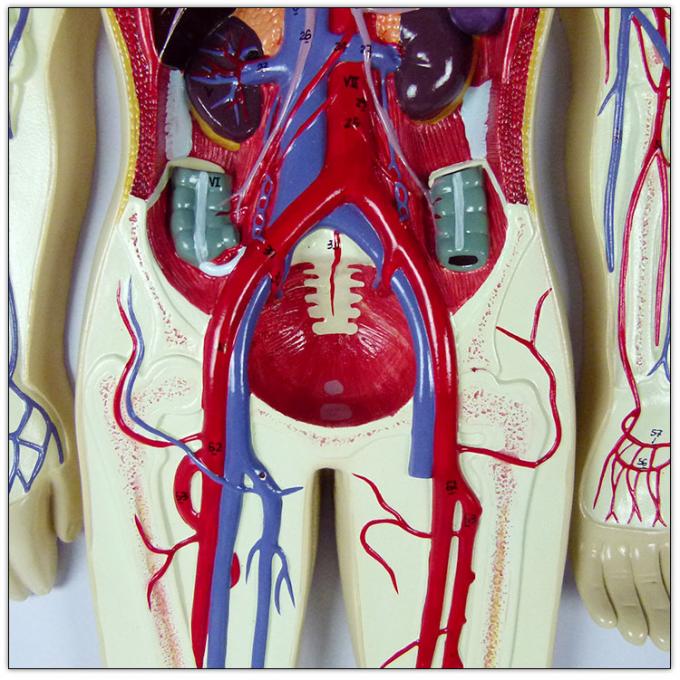

วันหัวใจโลก | Oldeenglishconsortium รูปแบบการสอนแบบระบบไหลเวียนโลหิตของมนุษย์ / การสอนแบบจำลองการไหลเวียนโลหิต

รูปแบบการสอนแบบระบบไหลเวียนโลหิตของมนุษย์ / การสอนแบบจำลองการไหลเวียนโลหิต รูปแบบการสอนแบบระบบไหลเวียนโลหิตของมนุษย์ / การสอนแบบจำลองการไหลเวียนโลหิต

รูปแบบการสอนแบบระบบไหลเวียนโลหิตของมนุษย์ / การสอนแบบจำลองการไหลเวียนโลหิต อวัยวะภายในและระบบไหลเวียนโลหิตของหญิงสาว ภาพประกอบสต็อก – ดาวน์โหลดรูป …

รูปแบบการสอนแบบระบบไหลเวียนโลหิตของมนุษย์ / การสอนแบบจำลองการไหลเวียนโลหิต รูปแบบการสอนแบบระบบไหลเวียนโลหิตของมนุษย์ / การสอนแบบจำลองการไหลเวียนโลหิต

รูปแบบการสอนแบบระบบไหลเวียนโลหิตของมนุษย์ / การสอนแบบจำลองการไหลเวียนโลหิต ฟิตเพิ่มเกรด ชีวะ ม.ปลาย – หัวใจเเละระบบหมุนเวียนเลือด – Dek-D’s School

ระบบไหลเวียนโลหิตในไตกายวิภาคศาสตร์เลือดกระดูกเชิงกรานไต, เลือด … ระบบไหลเวียนโลหิตของมนุษย์กายวิภาคหัวใจ ภาพสต็อก – ดาวน์โหลดรูปภาพ …

แบบจำลองระบบหมุนเวียนโลหิตของมนุษย์ – EnterCenterShop ระบบหมุนเวียนโลหิต

แสดงแบบจำลองกายวิภาคศาสตร์การไหลเวียนโลหิตรวมถึงระบบหัวใจและหลอดเลือด … โปสเตอร์เรื่องระบบไหลเวียนโลหิต โปสเตอร์ภาพประกอบการศึกษา โปสเตอร์การ …